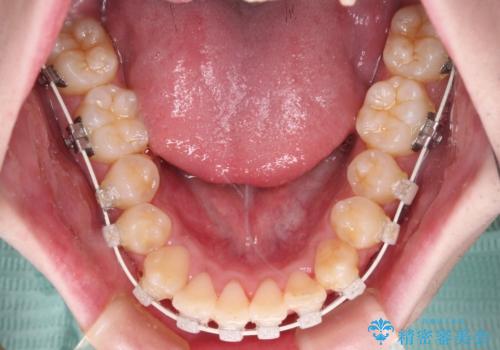

全顎的なクロスバイト 補助装置を用いてワイヤー矯正

前歯のクロスバイトや八重歯の他に、左右最後臼歯のシザーズバイト(鋏状咬合)が認められました。

シザーズバイト改善のために補助装置を使用しながら、ワイヤー装置にて全体の歯列を整えることとしました。

シザーズバイトは強く咬合する奥歯を移動させるため、多くの場合においてワイヤー矯正の装置のみでは改善が困難となります。

奥歯の咬み合わせ改善は治療初期からしっかりとアプローチする必要があるため、補助装置を積極的に利用します。